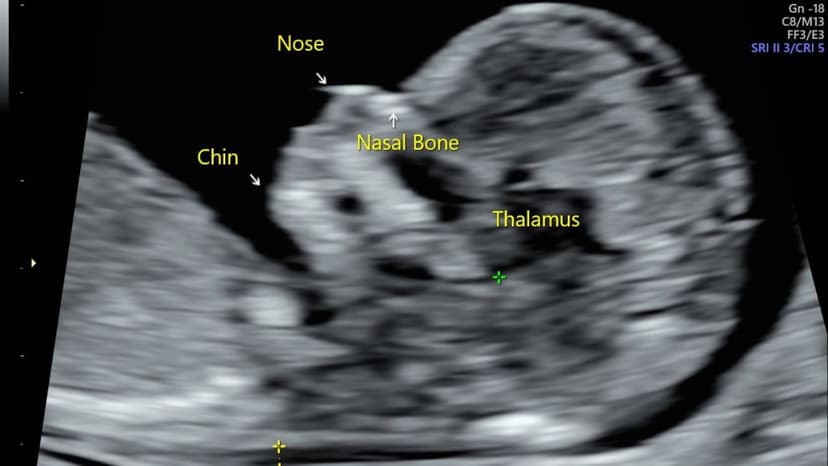

Chiều dài bàn chân của thai nhi được xác định là kích thước dài nhất tính theo trục dọc của bàn chân. Khi siêu âm, bác sĩ sẽ tiến hành đo khoảng cách từ phần gót chân đến đầu của ngón chân dài nhất (thường là ngón thứ nhất hoặc ngón thứ hai).

Theo tạp chí y học Cureus, phương pháp đo lường này được coi là một công cụ vô cùng tin cậy để ước tính tuổi thai. Thông số này đặc biệt phát huy tác dụng trong các trường hợp mà các chỉ số thông thường (như chu vi đầu, chiều dài xương đùi) khó đo đạc hoặc bị sai lệch do thai nhi có các bất thường về hình thái.

Trong thực tế thăm khám, việc đánh giá chiều dài xương bàn chân thai nhi thường không được sử dụng đơn lẻ mà sẽ kết hợp với các thông số khác để bác sĩ có góc nhìn toàn diện nhất. Các bằng chứng lâm sàng chỉ ra rằng, kích thước bàn chân có mối tương quan tuyến tính chặt chẽ với đường kính lưỡng đỉnh, chu vi vòng bụng và chiều dài xương đùi; mức độ tương quan này ngày càng tăng và biểu hiện rõ nét từ tuần thứ 10 đến tuần thứ 16.

Đặc biệt, tỷ lệ giữa chiều dài xương đùi và chiều dài bàn chân là một thông số cực kỳ quan trọng. Tỷ lệ này thông thường dao động trong khoảng từ 0.9 đến 1. Thông qua việc phân tích tỷ lệ chênh lệch này, bác sĩ có thể phân biệt được tình trạng thai nhi có chi ngắn chỉ đơn thuần do chậm phát triển hay là dấu hiệu cảnh báo của các vấn đề liên quan đến loạn sản hệ xương (đặc biệt nguy cơ cao khi tỷ lệ này tụt xuống dưới 0.92).